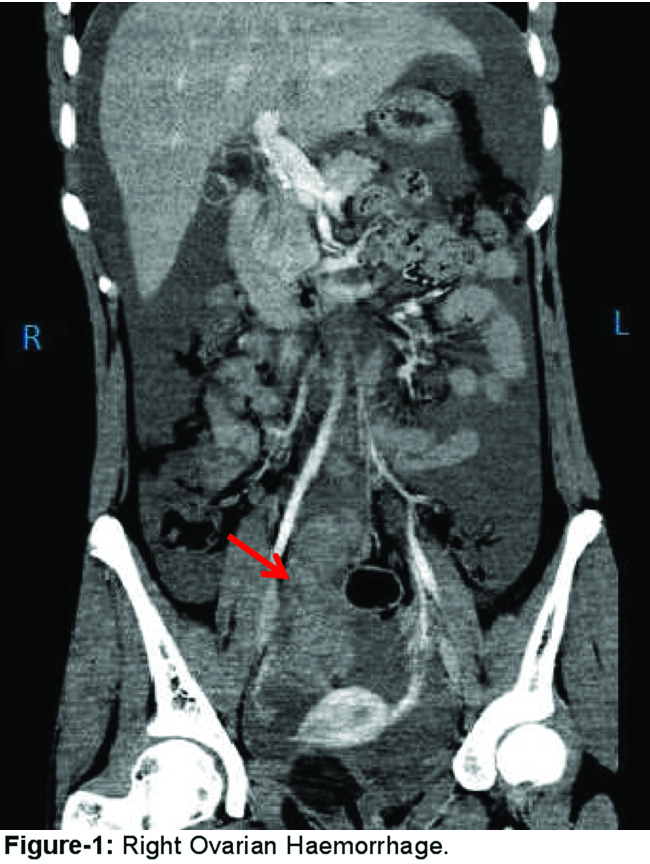

A 15-year old girl with a possible family history of bleeding tendency presented to emergency department (ED) with severe abdominal pain. There was no history of trauma.She was vitally stable. Abdominal examination revealed distension and tenderness. CT scan of the abdomen (Figure-1)

showed retroperitoneal haematoma representing right ovarian haemorrhage. Initial laboratory workup showed Hb 6.1g/dl: Platelet count, prothrombin time (PT), partial thromboplastin time (PTT) were in normal range. Her AFP, beta-HCG level along with vWF and ristocetinco-factor assay was normal. FXIII screen on 5Murea not deficient. She was managed conservatively with fresh frozen plasma (FFP) and packed cell. Her hospital course was uncomplicated. Follow up CT scan after one month showed resolution of previously noticed haematoma.